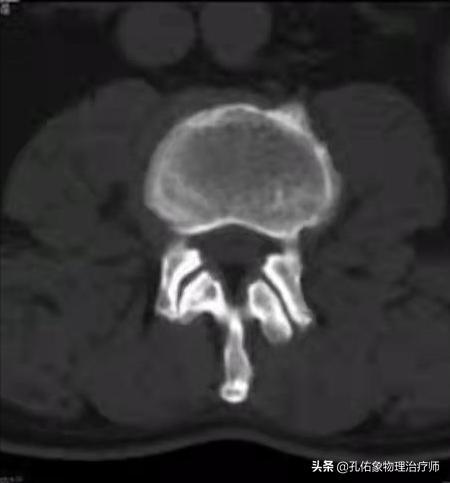

如上圖中所示,椎管在椎間盤(髓核+纖維環(huán))的后方,里面穿行脊髓;若是因?yàn)槟撤N因素使椎管變窄了,很可能會壓迫神經(jīng)、脊髓等。

常見導(dǎo)致椎管狹窄的因素主要有:

腰椎的椎體后緣增生,后縱韌帶的鈣化,小關(guān)節(jié)突增生,側(cè)隱窩狹窄,黃韌帶肥厚,椎管內(nèi)占位(腫瘤或間盤脫出)。